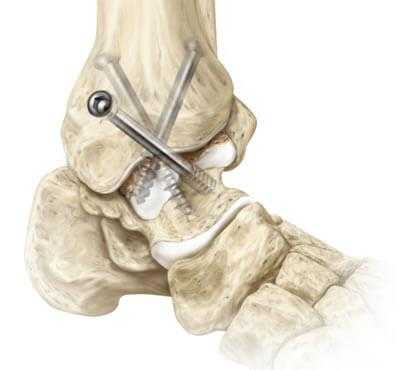

Обездвиживание достигается за счет жесткого соединения примыкающих концов костей сустава между собой специальными металлическими фиксаторами: спицами, винтами, штифтами. Это позволяет суставным поверхностям срастись друг с другом под нужным углом, то есть привести сочленение в полное неподвижное состояние, что снимает болевой синдром.

1. Внутрисуставный. Вскрытие капсулы сустава с последующим удалением поврежденного гиалинового хряща с поверхностей костных элементов. После репозиции костей в выгодном положении выполняется их фиксация металлическими приспособлениями.